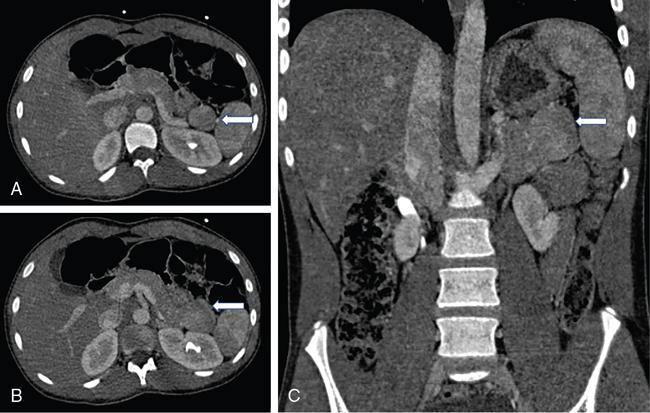

Kalpana Bansal, Poonam Narang The paediatric splenic abnormalities include both congenital and acquired pathological conditions. The congenital anomalies include variations in splenic number, location or fusion abnormalities and are more common than the acquired pathological conditions like splenomegaly, focal lesions, tumours and trauma. The splenic pathology can be evaluated with a wide variety of available imaging modalities including an ultrasound that is usually the first modality of choice in paediatric patients, computed tomography, magnetic resonance imaging and technetium-99m scintigraphy. The pattern-oriented approach to the radiological evaluation of splenic abnormalities may help to reach an accurate diagnosis and plan patient management. The congenital anomalies are common splenic abnormalities in paediatric patients. They usually result from absent or incomplete fusion of splenic lobules into one single organ before birth or abnormal location of the spleen. The congenital malformations include: The accessory spleen is commonly referred to as the splenunculus or supernumerary spleen. It results from the failure of the fusion of the primordial splenic buds in the dorsal mesogastrium during foetal life. The incidence is seen in 10%–30% of the population. The most common location of an accessory spleen is near the splenic hilum seen in about 75% of the cases and the pancreatic tail in 25% cases. It may be located anywhere along the course of the splenic vessels or in the abdomen and pelvis. The size of an accessory spleen ranges from few millimetres to centimetres and the number may vary from 1 to 6 (Fig. 9.21.1). The accessory spleens are usually asymptomatic and incidentally detected on imaging. But an accessory spleen present in an unexpected location can be misinterpreted as an abnormal soft tissue mass or lymph node. The characteristic imaging findings of the accessory spleen include similar imaging appearance to normal spleen on CT and MRI. The demonstration of feeding artery from the splenic artery can also be helpful in the differential diagnosis. Iron-containing MR contrast agents and Tc-99 sulphur colloid scintigraphy may be useful to confirm the diagnosis. The clinical significance of accessory spleen is seen in patients who had splenectomy for hypersplenism. In such patients, the accessory spleen may hypertrophy and result in recurrent disease; however, in patients of splenic trauma who had a splenectomy, it may help preserve the immune functions of the spleen. Splenopancreatic fusion is a rare anomaly that results due to abnormal fusion of splenic or pancreatic tissue as both organs arise from the dorsal mesogastrium close to each other. The ectopic splenic tissue may be located in the pancreatic tail (Fig. 9.21.2) and ectopic pancreas in the spleen or accessory spleen. It is also an incidental finding and asymptomatic. The clinical importance is to avoid complications during splenectomy or distal pancreatectomy. Splenogonadal fusion is an extremely rare anomaly that results due to the persistence of splenic tissue between the spleen and left testicle or epididymis. It may simulate masses and warrant unnecessary surgeries. The demonstration of splenic tissue connecting the spleen with the left gonad using any of the imaging modality helps in definitive diagnosis. Wandering or ectopic spleen is an extremely rare entity that results due to laxity or maldevelopment of the supporting splenic ligaments, and spleen can be found in any part of the abdomen. The incidence in several large studies of splenectomy is less than 0.5% and is mainly seen in children. The wandering spleen may be detected incidentally or present with different degrees of abdominal pain related to intermittent or acute torsion of the vascular pedicle. Ultrasound and CT remain the mainstay of diagnosis. Imaging findings include the absence of spleen in its normal position and a mass located anywhere in the abdomen or pelvis showing imaging and enhancement characteristics of normal splenic tissue. Besides, in the case of torsion, a typical ‘whirl’ pattern of the twisted pedicle and altered enhancement may also be demonstrated. Doppler shows absent flow within the spleen and low diastolic velocity with raised resistive index in the proximal splenic artery. The unenhanced CT shows hypoattenuation of the spleen, hyperdense intraluminal thrombus in the splenic artery and high density of the splenic capsule relative to parenchyma (‘rim’ sign). The contrast-enhanced CT shows absent or heterogeneous enhancement. The treatment modality of choice is splenopexy; however, splenectomy may be indicated in cases of infarction. Polysplenia and asplenia are typically seen in association with situs ambiguous or heterotaxia. Situs ambiguous with asplenia also known as Ivemark syndrome refers to right isomerism or bilateral right-sidedness and is characterized by an ambiguous location of abdominal organs with congenital absence of the spleen. It is more prevalent in males and associated with congenital heart disease in almost all cases (Fig. 9.21.3). Most patients die within the first year of life due to associated severe congenital heart disease and immunodeficiency due to absent spleen. Situs ambiguous with polysplenia is referred to as left isomerism or bilateral left sidedness. It is more common in females. The spleen may be located on the left or right side of the upper abdomen, the number may vary from 2 to 6 and diameter ranges from 1 to 6 cm (Fig. 9.21.4). The coexisting anomalies include a right-sided stomach, a midline or left-sided liver, bowel malrotation, short pancreas, absent gallbladder and associated inferior vena cava anomalies. Splenosis is an acquired anomaly that occurs following splenic trauma or splenectomy. It results due to auto-transplantation of splenic tissue usually in the peritoneal cavity but also may occur in extraperitoneal locations like the thoracic cavity. Splenosis is usually asymptomatic and incidentally detected on imaging. Splenosis is an acquired condition so it has distorted architecture and is supplied by surrounding vessels so, it can be mistaken for neoplastic lesions and lead to unnecessary surgery. A patient who had splenectomy for hypersplenism, splenosis may result in recurrent disease. However, a functioning splenic tissue may be required to preserve normal immunological function and remove old blood cells. Splenomegaly is a nonspecific finding seen as a manifestation of various disease processes listed in Box 9.21.1. CAUSES OF SPLENOMEGALY Ultrasound is usually the first and useful modality to evaluate enlarged spleen. It accurately measures the splenic span and also assesses the splenic echotexture, homogeneous or heterogeneous. Doppler USG is very good for the assessment of portal hypertension as a cause of splenomegaly by demonstrating flow in the splenoportal axis and collaterals. Both USG and CT also assesses the ancillary findings like lymphadenopathy in case of lymphoma or tuberculosis. Portal hypertension is one of the most common noninfectious causes of splenomegaly in children. Patients usually present with significant gastrointestinal bleed or massive splenomegaly. The causes of portal hypertension may be prehepatic, intrahepatic or posthepatic. The portal vein thrombosis is mostly idiopathic in children and results in collateral vessel development at porta known as cavernous transformation of the portal vein or portal cavernoma and portosystemic collaterals with massive splenomegaly (Fig. 9.21.5).